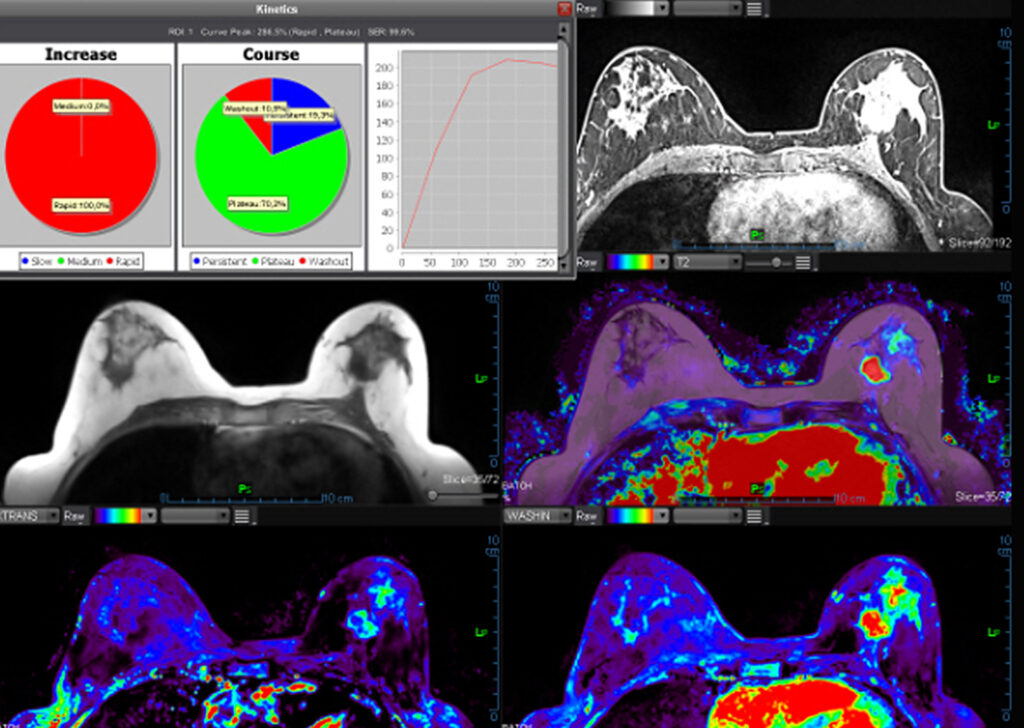

MR Breast (Basic)

Olea MR Breast applications are efficient tools for breast lesion detection, characterization and staging. Olea MR Breast applications are efficient tools for breast lesion detection, characterization and staging.

MR Breast Advanced (breastscape®)

This is a semi-automated solution for diagnostic assistance in breast lesions. Automatically computes parametric maps, segmentation of lesions and calculation of distances, lesion evolution follow-up, preparation of BI-RADS® Atlas.